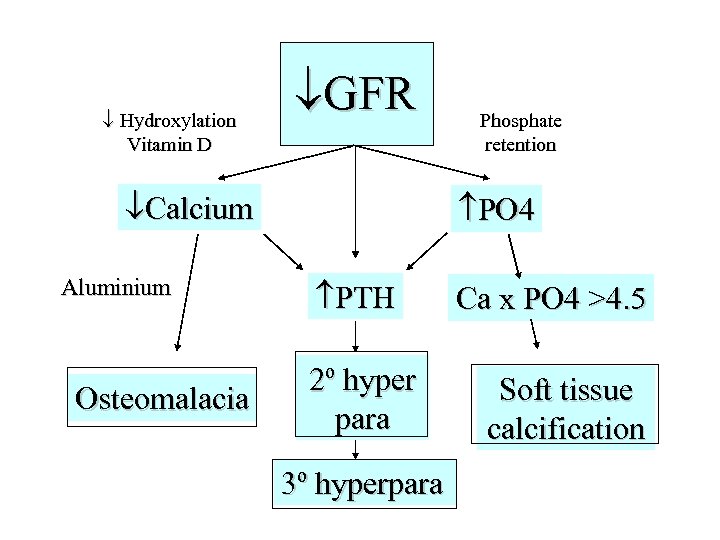

Hydroxylation Vitamin D GFR Calcium Aluminium Osteomalacia Phosphate retention PO 4 PTH 2º hyper para 3º hyperpara Ca x PO 4 >4. 5 Soft tissue calcification

Hydroxylation Vitamin D GFR Calcium Aluminium Osteomalacia Phosphate retention PO 4 PTH 2º hyper para 3º hyperpara Ca x PO 4 >4. 5 Soft tissue calcification

Clinical features • May be none • Soft tissue calcification - itch, red eye, calciphylaxis and (probably) increased risk CHD due to coronary calcification • 2 y hyperpara - high PO 4 with low Calcium, may cause bone pain, fractures • Osteomalacia - bone pain, rickets in childhood, proximal myopathy, fractures NB Osteitis fibrosa cystica is the term used to describe the appearance of bone in 2 y hyperpara. In severe cases, proliferation of osteoclasts results in cyst formation in bone called a “brown tumour” which is not premalignant

Clinical features • May be none • Soft tissue calcification - itch, red eye, calciphylaxis and (probably) increased risk CHD due to coronary calcification • 2 y hyperpara - high PO 4 with low Calcium, may cause bone pain, fractures • Osteomalacia - bone pain, rickets in childhood, proximal myopathy, fractures NB Osteitis fibrosa cystica is the term used to describe the appearance of bone in 2 y hyperpara. In severe cases, proliferation of osteoclasts results in cyst formation in bone called a “brown tumour” which is not premalignant